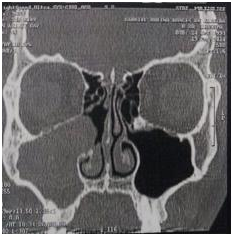

The lesion extended to nasal cavity, involving the medium turbinate obliterating the ostiomeatal complex. Left nasal cavity and sinus showed no alterations (Figure 1&2). Tomography conclusion suggested chronic sinusopathy caused by fungus or polyps. Transnasal endoscopic surgery combined with Cadwell Luc approach was performed based on the tomography images. The lesion was easily avulsed from adjacent tissue and removed completely. It was sent to anatomophatological analysis. Gross examination of the specimen revealed a friable, reddish brown coloured single lesion with elastic density. The microscopic examination disclosed squamous mucosa with chronic inflammation, an endothelial cell proliferation with papillary formations and areas of haemorrhage and neovascularization (Figure 3). There was no complication on postoperative course. The patient had no recurrence of the symptoms after 12months past the surgery.

Figure 1 Coronal TC of the paranasal sinuses showing maxillary opacification with extension to nasal cavity, involving the medium turbinate.